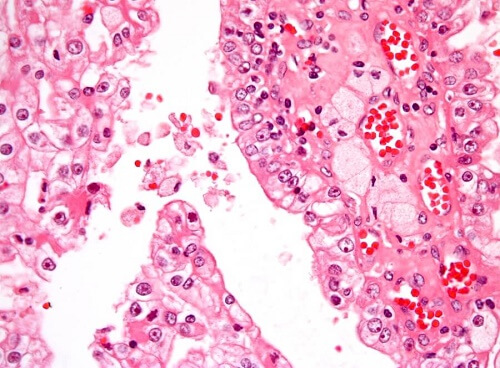

Il tumore si verifica quando c’è una moltiplicazione di cellule maligne, fuori controllo, nel corpo. Il tipo più comune di tumore ai reni nell’infanzia si chiama tumore di Wilms o nefroblastoma. È di consistenza solida e ha origine nel tessuto renale immaturo.

In base a quanto indicato dallo specialista, verrà eseguita anche una biopsia tumorale, con un ago perforante, in modo da prelevare cellule o tessuti per l’analisi microscopica da parte di un patologo.